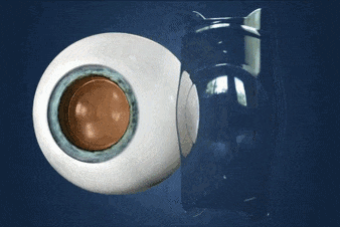

EVO是原ICL人工晶体植入技术上晶体材料的一次全新升级,是一种由Collamer专利胶原聚合材料制作而成的柔软晶体,它可矫正50-1800度近视,600度以下散光,矫正范围比激光更广,是众多高度近视患者的摘镜的选择!

而最新一代的 EVO+ ICL(V5)晶体 更进一步优化了设计:

1、光学区扩大,夜间视觉质变

V4C的光学区直径为4.9-5.8mm,而V5则将光学区扩大至5.0-6.1mm。这一看似微小的调整(约0.3mm),却能为特定人群带来显著的夜间视觉提升。

2、25度精细矫正,中低度近视也适配

实现了更精细的度数矫正步长。对于600度以下的中低度近视患者,矫正精度从以往的50度一档,提升至25度一档。为追求极致视觉质量的中低度近视患者提供了更理想选择。

EVO+ ICL(V5)晶体在保留原有安全、可逆、视觉质量优等特点的基础上,通过光学设计的进步,进一步提升了术后视觉体验,尤其适合对夜间视力要求较高的人群。